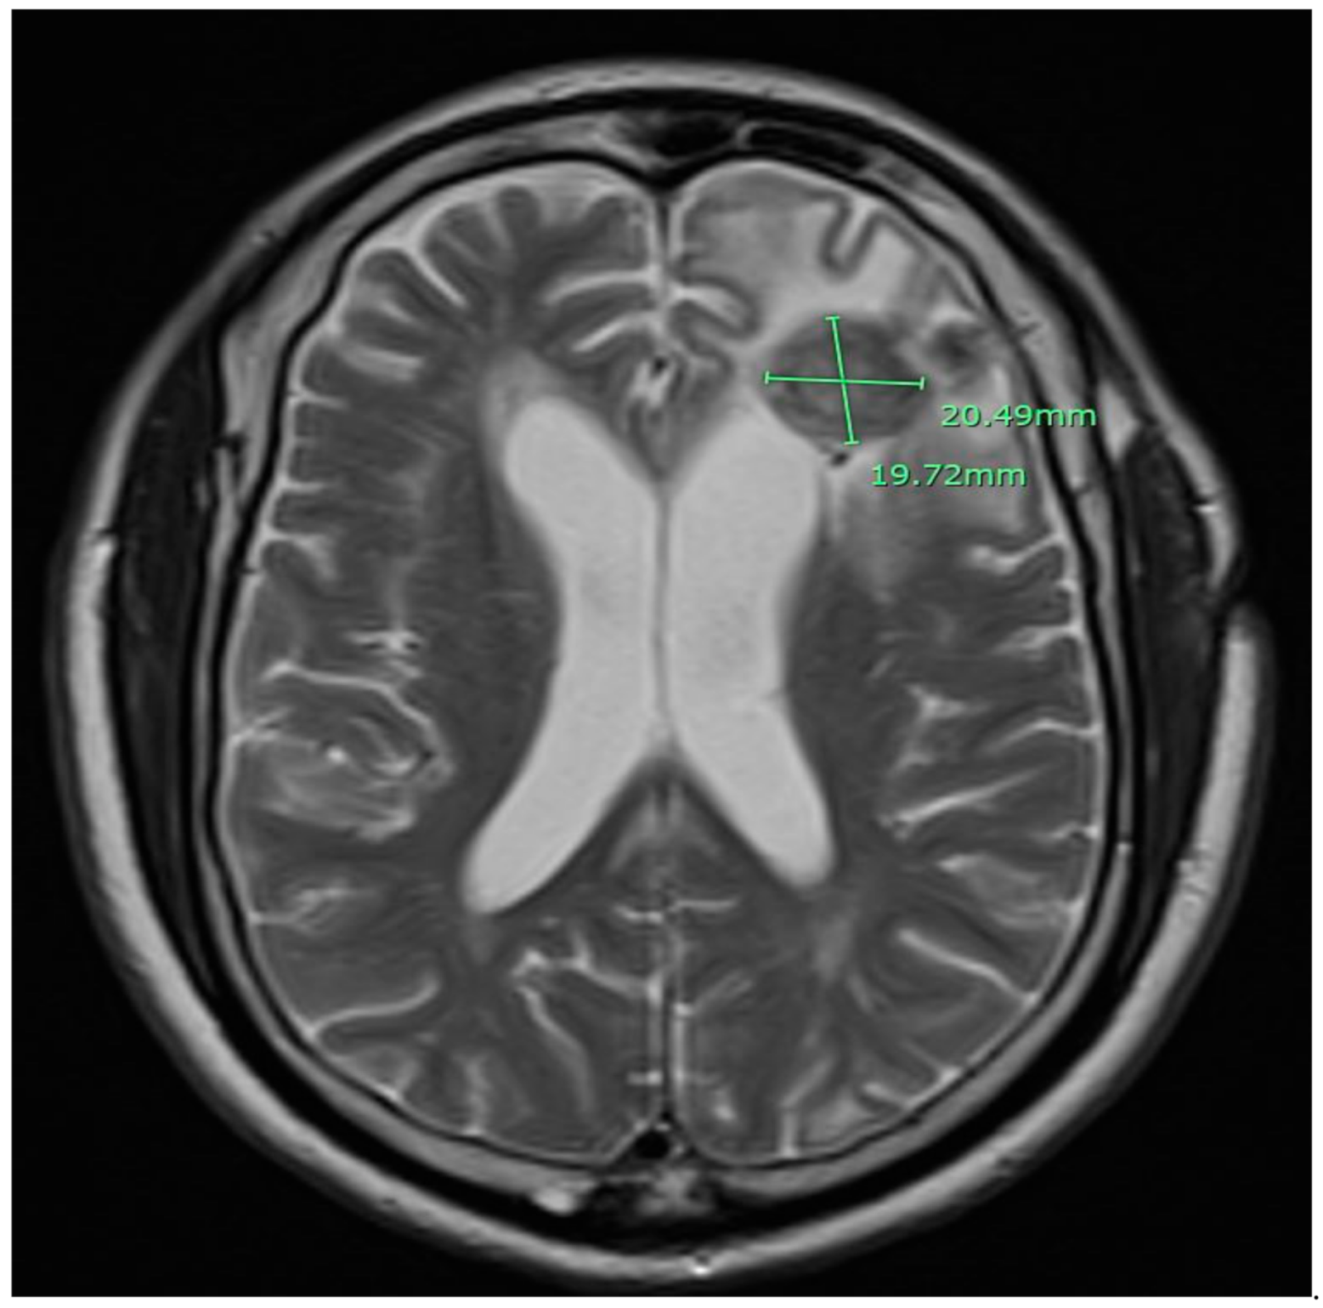

2. Case Presentation